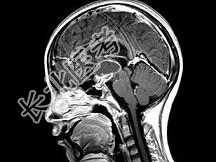

- 单项选择题女,18岁, 发育不良伴口渴,多饮、多尿10余年, 根据所提供图像,最可能的诊断是 ( )

C、颅咽管瘤